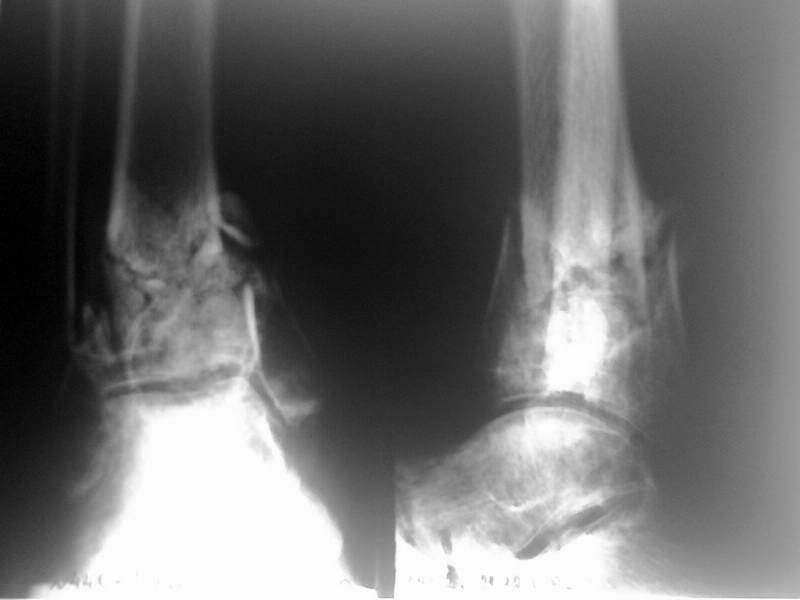

Доброго времени суток! Хотелось бы посоветоваться по срокам и тактике лечения пациента с переломом пилона 6 месячной давности. Пациент 50 лет, получил травму в июле 2008г. - упал с высоты 2 м, подвернул ногу. Лечился вытяжением в соседнем отделении, через 4 недели был загипсован и отправлен восвояси. Через 3 месяца в поликлинике ему сняли гипс и заставили ходить с нагрузкой на ногу, чего он сделать не смог - нога подворачивается, сильных болей нет. Через 6 месяцев с момента травмы пациент сообразил, что что-то идет не так, и сам пришел к нам с вопросом - "Что делать?" При осмотре имеется тугая подвижность в зоне перелома, движения в голеностопном суставе ограничены, острых болей нет. Отек стопы и голени умеренный. Операция назначена на 27 января, планируем наложение аппарата Илизарова для устранения смещения по оси и длине, затем планируется накостный остеосинтез большеберцовой и малоберцовой. Но возникает ряд вопросов. - Оптимальные сроки накостного остеосинтеза?- Фиксаторы? Лист клевера и обычная пластина на малоберцовую или искать LCP? - И совсем уж крамольный вопрос - нужен-ли накостный остеосинтез для восстановления анатомической целостности в принципе, через 7 месяцев после травмы?

На снимке типичный перелом пилона с компрессией метафиза и с укорочением берцовой кости. Свежие переломы пилона лечатся восстановлением длины малоберцовой и с замещением дефекта большеберцовой структурным пластическим материалом. Обычная аутокость или синтетические заполнители служат пластическим материалом. В зависимости от перелома пластину устанавливают медиально или латерально.

Без восстановленного метафизарного дефекта перелом пилона со временем коллапсируется, а малоберцовая удерживает нагрузку и конечность деформируется в варус.